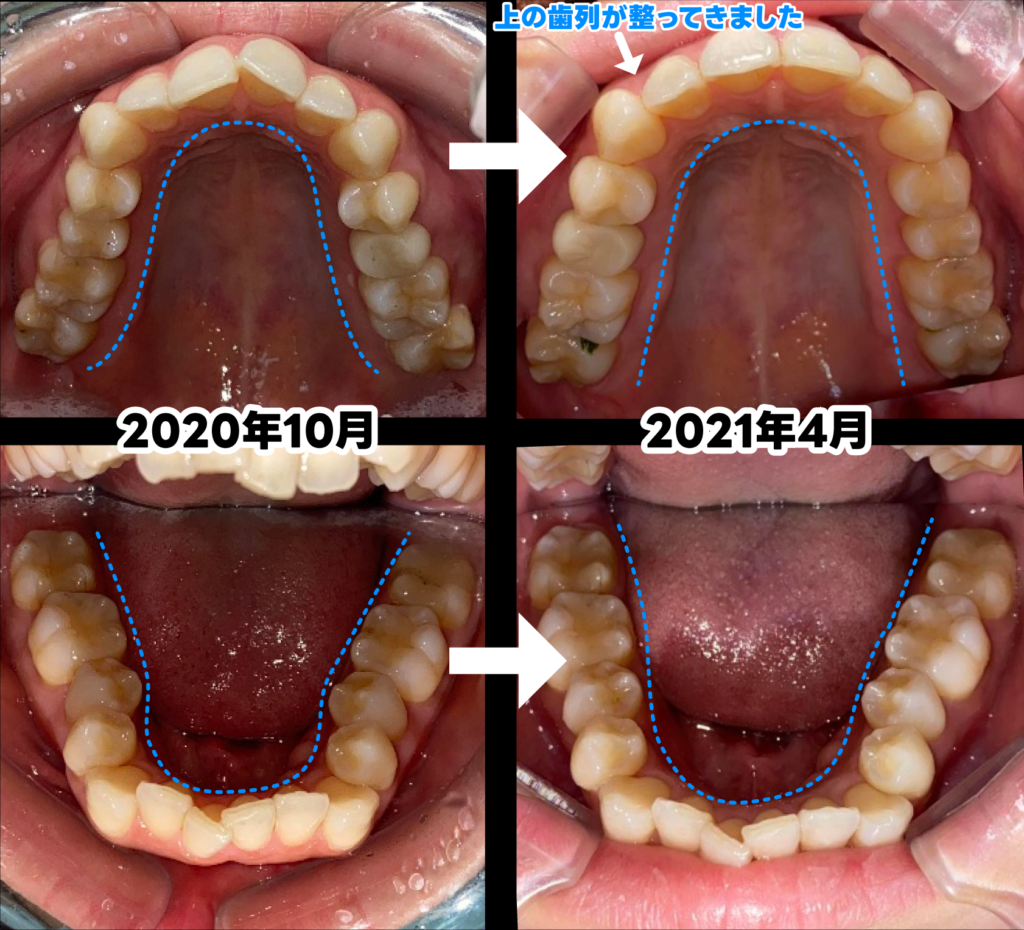

【2020年10月】

アライナーの装着を開始しました。

【2021年4月】

アライナー装着から7ヶ月が経過し、歯並びのアーチがきれいに仕上がってきました。

アーチが広がりV字型からU字型になったのがわかります。